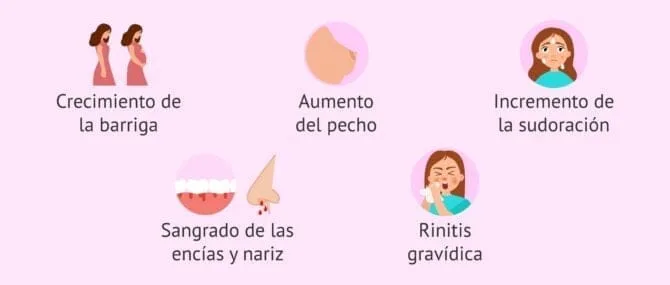

Test de embarazo como y cuando hacerlo MD.Saude hotsell, Semana 14 de embarazo sintomas y desarrollo del bebe Dodot hotsell, Calendario de Embarazo semanas 1 2 y 3 Pampers hotsell, Cuando hacer un test de embarazo para que sea fiable hotsell, Semana 14 de embarazo inicio del segundo trimestre hotsell, Creo que estoy embarazada Test de embarazo online para despejar dudas hotsell, Gestograma Calculadora semanas y dias del Embarazo Natalben hotsell, Semana 3 de embarazo inicio del desarrollo del embrion hotsell, Creo que estoy embarazada Test de embarazo online para despejar dudas hotsell, EMARLAN hotsell, Calcular la ovulacion El mejor momento para quedar embarazada YouTube hotsell, Semana 1 de embarazo cuales son los sintomas en la madre hotsell, Cuanto se tarda en lograr un embarazo tras mantener relaciones hotsell, Como saber si estoy embarazada de pocos dias 18 signos mas comunes hotsell, Sintomas de embarazo pero test negativo posible falso negativo hotsell, Como saber si estoy embarazada de pocos dias 18 signos mas comunes hotsell, Cuando hacerse un test de embarazo hotsell, Cuando hacerse un test de embarazo hotsell, Como puedo saber si estoy embarazada Centro Medico ABC hotsell, Semana 1 de embarazo cuales son los sintomas en la madre hotsell, Cuando hacer la prueba de embarazo DKV hotsell, Es posible quedar embarazada durante los dias no fertiles Next Fertility hotsell, Estoy embarazada pero nunca perdi mi periodo menstrual hotsell, Semanas 1 2 y 3 de embarazo Pampers hotsell, Cuando hacer un test de embarazo para que sea fiable hotsell, Periodo con retraso o embarazo Vamos a averiguarlo hotsell, Cuantos dias de retraso son normales para saber si estoy embarazada hotsell, Cuando hacer la prueba de embarazo DKV hotsell, Semana 2 de embarazo lo que debes saber Hero hotsell, Semana 1 de embarazo cuales son los sintomas en la madre hotsell, Semanas 1 2 y 3 de embarazo que es lo que te espera Dodot hotsell, Primeros sintomas de embarazo antes del retraso menstrual hotsell, Primeros sintomas de embarazo antes del retraso menstrual hotsell, 14 dias tras la ovulacion como detectar si estas embarazada hotsell, Cuando hacer la prueba de embarazo DKV hotsell, Product Info: En 14 dias puedo saber si estoy embarazada hotsell.